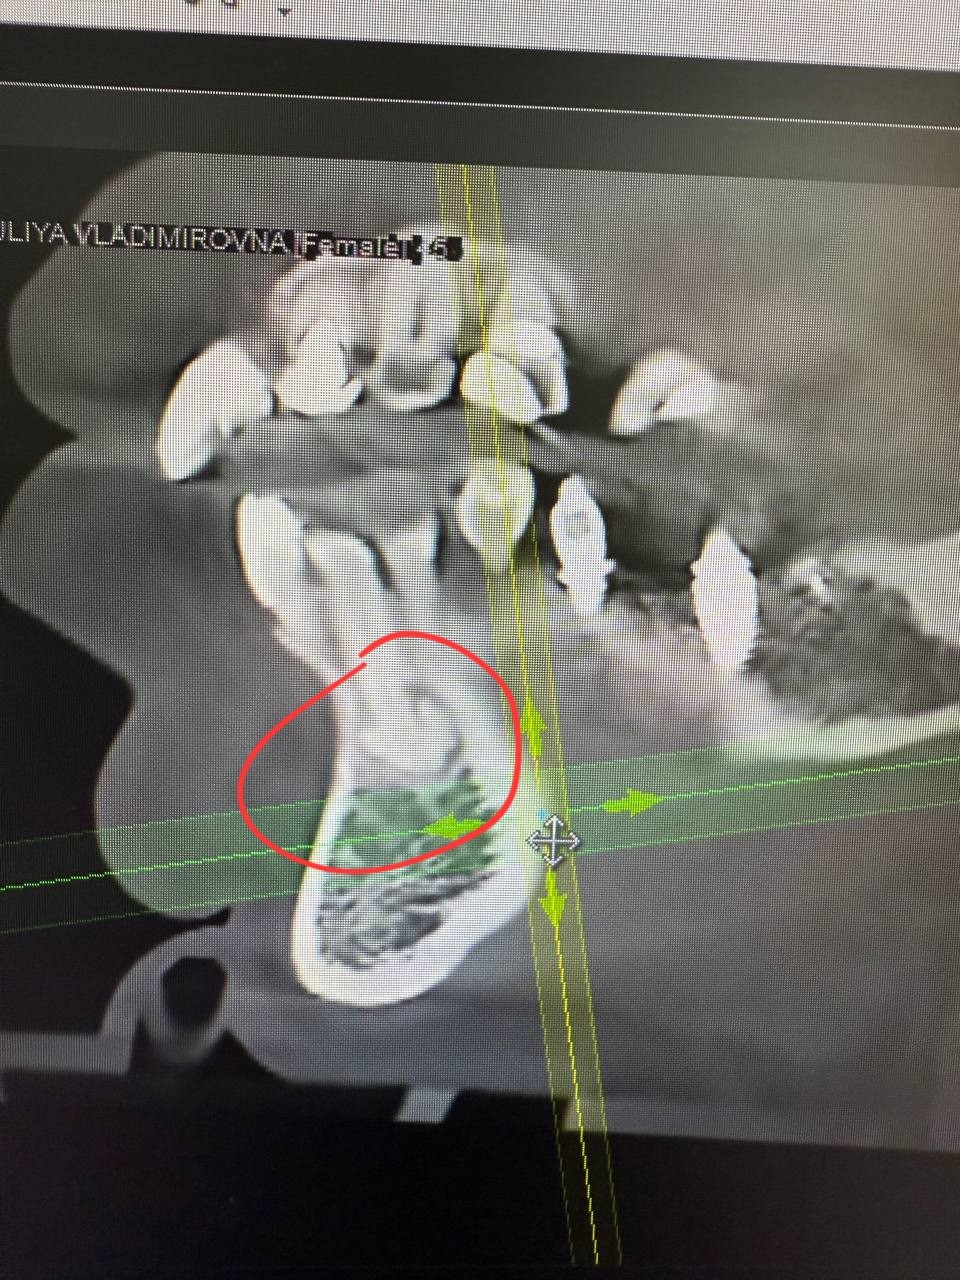

Здравствуйте, прохожу протезирование коренных зубов. КТ показало образование на корнях зубов 12 и 43. Врач затрудняется ответить что это может быть.

Вверху предположительно цементома, а внизу предположительно одонтома. Это все доброкачественные состояния. У вас получится прислать все содержимое диска с КТ через файлообменник, например, гугл-диск?

Мой лечащий врач склонен считать что это цементно костная дисплазия и в верху и внизу. Предлагает не трогать и смотреть в динамике как образование будет себя вести в дальнейшем (это вверх). Низ просто под наблюдением, там коронок не будет. Если будет рост на корне 12, возможна резекция корня с последующей гистологией. Как бы решать проблему по мере поступления.